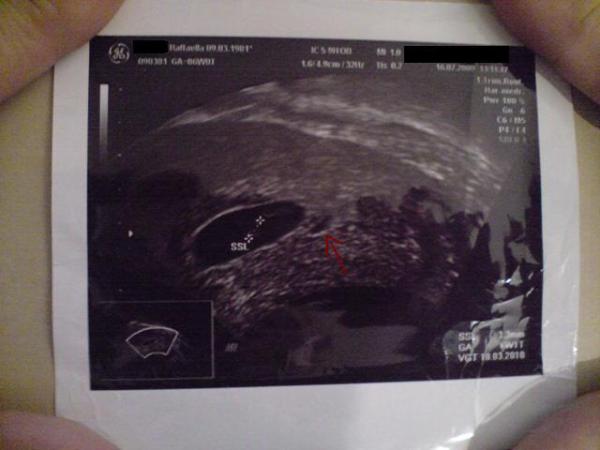

was ihr vermutet.... ich starre jetzt seit tagen auf mein US-Bildchen. Rechts unterhalb von der Fruchhöle sieht man wie eine kleine Blase.... Mein Gyno meinte es könnte Gewebe sein oder eine versteckte Fruchthöle.. Muss noch dazusagen das ich schon vor dem US-Termin tagelang ein Bauchgefühl habe das ich mehrlinge bekomme. Seit Tagen/Nächte träume ich auch von mehrlingen. Und diese Kombi US-Bildchen/Bauchgefühl/Träume bringt mich fast um den Verstand...... Mein Gyno ist noch 2 Wochen in den Ferien.... muss also noch 2 wochen lang über mein US bildchen rätseln.... rätselt ihr mit??? LG Raffaella

Bild zu jetzt muss ich doch euch mal fragen... - Forum für März - Mamis